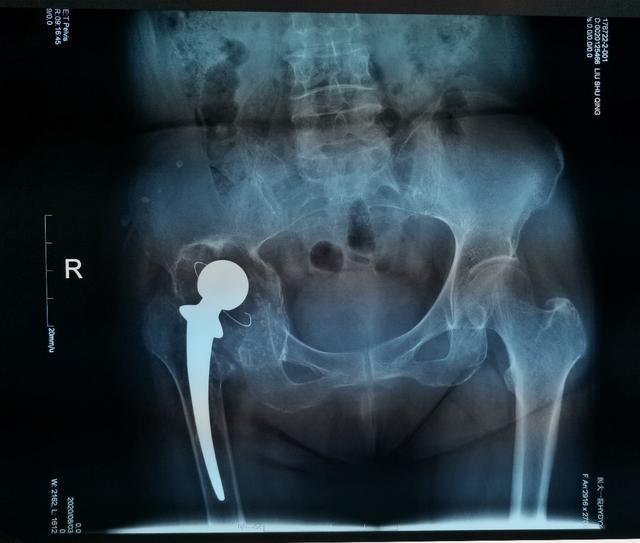

對于復(fù)雜髖關(guān)節(jié)翻修多為高齡患者,由于骨缺損巨大、骨質(zhì)疏松等因素,存在手術(shù)難度大、手術(shù)費用高等難題。近日,哈醫(yī)大一院骨科一病房3D打印團隊,應(yīng)用3D打印技術(shù),通過術(shù)前打印骨骼模型進行模擬假體安裝,成功為一名70歲,全髖關(guān)節(jié)置換術(shù)后15年,髖臼骨缺損巨大,髖臼上部坐骨、髂骨存在巨大空洞型缺損的患者實施了我省首例金屬3D打印三翼髖臼假體(Triflange)+股骨柄假體髖關(guān)節(jié)翻修術(shù),為患者更換了一個新的、穩(wěn)定的髖關(guān)節(jié)。目前患者已康復(fù)出院。

70歲的劉阿姨十五年前因股骨頭壞死進行了全髖關(guān)節(jié)置換手術(shù)。五年前右腿開始有明顯的縮短,髖部疼痛也逐漸加重,來到哈醫(yī)大一院時已經(jīng)無法行走。經(jīng)影像檢查,患者十五年前采用水泥固定髖臼杯,金屬頭和聚乙烯髖臼杯十?dāng)?shù)年的摩擦產(chǎn)生的聚乙烯碎屑已經(jīng)導(dǎo)致髖臼巨大的骨缺損,假體上移,不僅髖臼,甚至坐骨,髂骨都有骨溶解,屬于Paprosky·3B型髖臼側(cè)骨缺損。此類疾病的治療主要采用三翼髖臼假體(Triflange)。由于患者髖臼骨缺損巨大,特別是在髖臼上部存在巨大的空洞型缺損,傳統(tǒng)的Triflange假體不能滿足劉阿姨髖臼的穩(wěn)定支撐和重建,且患者骨質(zhì)疏松,傳統(tǒng)假體骨長入能力難以滿足要求。